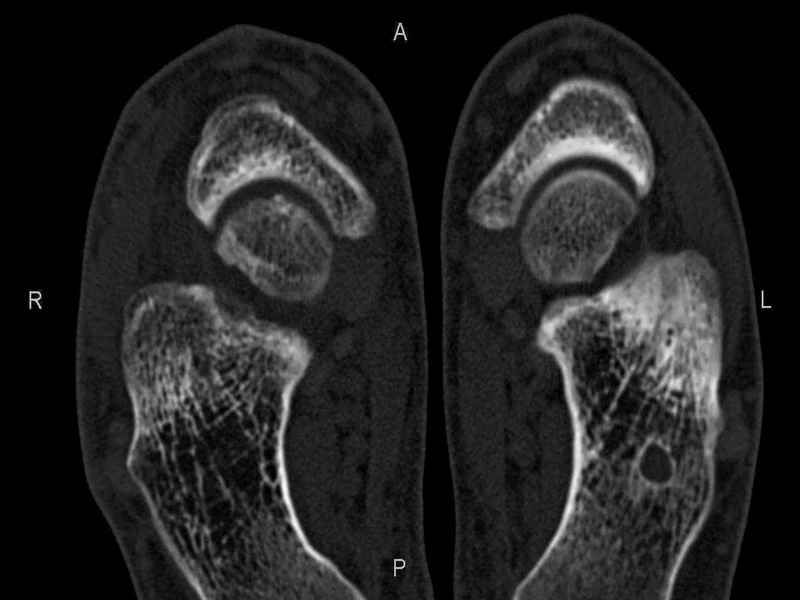

Уважаемые коллеги, обратился за помощью пациент, мужчина, 25 лет. С жалобами на болевой синдром в области голеностопного сустава и среднем отделе стопы. Травму отрицает. Со слов, болевой синдром в течении 1 года. Последние 1-1.5 мес периодически вынужден пользоваться костылями. После ограничения нагрузки боли уменьшаются.Соматически здоров. До появления болей активно занимался рукопашным боем. На СКТ картина рассекающего остеохондрита блока таранной кости, киста шейки таранной кости с признаками импрессии суставной поверхности. А также - разрастания переднего края б\берцовой кости сопровождающиеся клиникой импиджмент синдрома. Предполагаемый план лечения- удаление свободного фрагмента суставного хряща из трансмаллеолярного доступа с рассверливанием поверхности дефекта, кюретаж кисты шейки с заполнением полости биокомпозитом + дебридмент переднего отдела голеностопного сустава. Прошу высказать своё мнение, за и против, предполагаемого плана лечения. А также по возможности ответить на вопросы: 1. Есть ли необходимость в улучшении васкуляризации таранной кости (например подтаранный артродез). 2. Учитывая планируемое применение биокомпозитного цемента целесообразно ли заполнение им дефекта блока таранной кости с моделированием края суставной поверхности.

СТ чётко демонстрирует секвестр, но открыв сустав вероятно, что хрящ тарана окажется интактным и только пальпацией/ ЭОП можно будет

идентифицировать локализацию секвестра. Если вы с этим столкнетесь, то секвестрэктомию я бы предложил сделать не со стороны суставной поверхности тарана, а со стороны угла тарана, субхондрально кюрретаж стенок, разнонаправленную туннелизацию спицей или 1.1мм сверлом и заполнить дефект спонгиозным графтом.

- киста шейки тарана, как вы думаете, какова её природа : аваскулярный некроз? эхинококк?